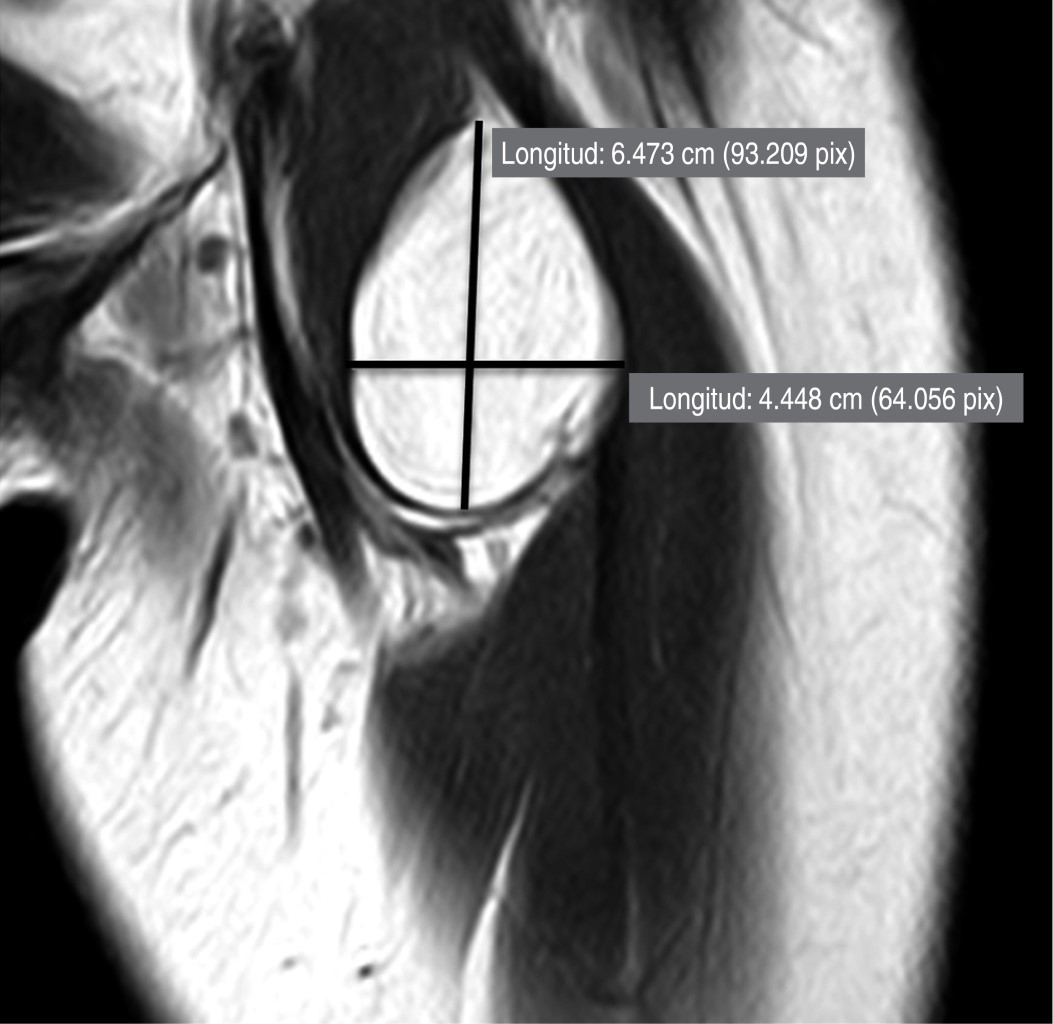

Se solicitó resonancia magnética nuclear (RMN) de muslo izquierdo, se encontró una masa lobular y tejido fibroso que atraviesan dichos lóbulos de aproximadamente 6.4 × 4.4 cm, con aumento de intensidad de la señal en T1 sin infiltración del tejido muscular circundante (Figura 1). Por los hallazgos clínicos y de imagen se decidió realizar resección quirúrgica de la lesión.

Figura 1